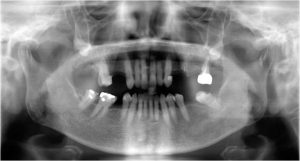

- 術前

- 術後

- インプラント手術直後のレントゲン